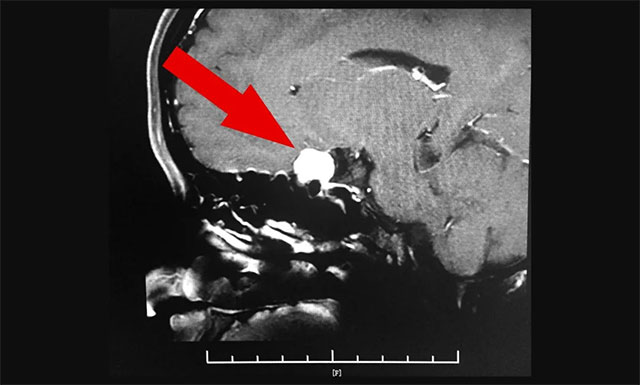

隨后,完善其各項檢查,為了進一步確定患者腦膜瘤位置和大小,進行了鞍區(qū)MRI平掃+增強,其左側鞍旁可見團狀腫塊影,T1WI呈等信號,T2WI呈等信號,部分低信號,邊緣清晰,大小約為1.5厘米x1.4厘米x1.5厘米,增強后病灶顯著,均勻強化,與同側海綿竇部分貼附。

腦膜瘤已壓迫患者左側視神經,需及時手術治療

▲ 腦膜瘤已壓迫患者左側視神經,需及時手術治療

根據魏女士的具體病情,其左眼視力為0.1,且已出現(xiàn)了視物模糊、重影等癥狀,并結合其影像檢查結果,潘仁龍主任、李士其教授及吳治群博士一致認為,應及時為患者手術,以防止其腦膜瘤進一步增大引起激素水平紊亂,視野缺損等嚴重并發(fā)癥。且鞍區(qū)腦膜瘤一旦確診應盡早手術,腫瘤越小,手術效果越好,術后視力恢復越理想。